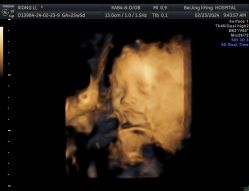

• 北京俪婴妇产医院(朝阳大悦城店)

lfmtliu 上传于 24-02-24 | 报错